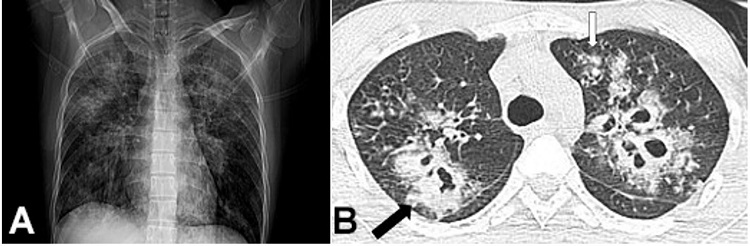

Approximately 25 days after the alleged assault, the patient was brought to the outpatient department complaining of fever, productive cough, and shortness of breath for the past 15 days, and weakness on the left side of his body. He did not have any ear pain, discharge, or nose block. He denied any history of recurrent diarrhea or respiratory infections since childhood. He was not a smoker or drug abuser and did not have any past respiratory illness. He had been working at a construction site for 3 months before the illness. On examination, his Glasgow Coma Scale (GCS) score was 15, and the central nervous system examination revealed left hemiparesis. Non-contrast brain computed tomography showed hypodensity in the right frontal and parietal region adjacent to the ventricle. A chest x-ray showed bilateral heterogeneous infiltration of the lungs (Figure 1A). A high-resolution chest computed tomography showed bilateral nodules of varying size and multiple cavities. The abnormalities were evident in both lungs, mainly in the bilateral upper lobes. There was no pleural effusion or significant mediastinal lymphadenopathy (Figure 1B). He was managed with broad-spectrum antibiotics. The diagnostic possibility of tuberculosis was considered, and empirical anti-tuberculosis treatment was started. Five days later, his GCS score deteriorated to 7 and he was admitted to the ward. Cerebral spinal fluid analysis showed 2,100 cells (reference range [RR]: 0–5 cells/mm3) with a predominance of lymphocytes, the glucose of 95 mg/dL (RR: 50–80 mg/dL), proteins of 16 mg/dL (RR: 15–40 mg/dL). Serological investigations for HIV, and hepatitis B and C were negative. A hemogram showed a total leucocyte count of 10,300/mm3 and a differential count was within normal limits; the hemoglobin was 14.4 mg/dL (RR; 13-15 g/dL) and the platelet count was 219,000/μL (RR 150,000-450,000/ μL). His liver function tests and renal function tests were within normal limits. On the third day of hospitalization, he succumbed to the illness. The autopsy was performed owing to the legal implications of this patient's case.

On external examination, the deceased was 173 cm in length and of average build. We observed a linear scar of 6.5 cm vertically over the left side of the forehead and the scalp’s frontal region. On reflecting the scalp, the scar was seen extending up to the periosteal layer of the skull bone. No underlying skull fracture was seen. There was no intracranial hemorrhage on internal examination; the brain was edematous weighing 1600 g (RR; 1075-1685g) and no basal exudates were seen. On the brain cut section, we noted an area of hemorrhagic necrosis in the right frontal and parietal lobes involving the corpus callosum, basal nuclei, lateral ventricle, and thalamus. The midline shift and compression of the adjacent brain parenchyma were noted. An area of necrosis with purulent exudate was seen in the cerebral cortex of the right temporal lobe (Figure 2A). Both lungs were enlarged and of hard consistency. The right lung weighed around 1050 g (RR: 360–570 g) and the left lung 1000 g (RR: 325–480 g). Multiple yellowish-white nodules were present on the surface and the cut section, and some nodules showed necrosis (Figure 2B). The hilar lymph nodes were slightly enlarged, and extensive consolidation was present in both lungs. Some cavitary lesions filled with necrotic material were present in the upper lobes of both the lungs. No pulmonary embolism or lung infarction could be seen. The heart and coronary arteries were grossly normal; the liver was enlarged, congested, and weighed 1730 g (mRR; 1540 g); the spleen and both kidneys were grossly normal except for some congestion.